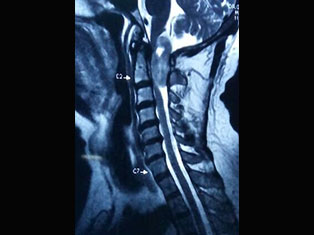

Spinal Tumors

A spinal tumor is a growth that develops within your spinal canal or within the bones of your spine. A spinal cord tumor, also called an intradural tumor, is a spinal tumor that that begins within the spinal cord or the covering.